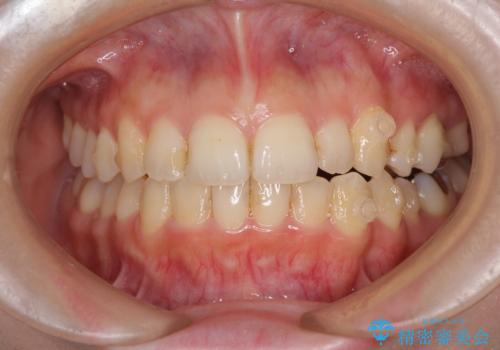

顕著な八重歯をインビザラインで治せるところまで改善

- 顕著な八重歯など、上下前歯のデコボコとスペースを気にして来院された患者様です。

八重歯改善には第一小臼歯の抜歯が必要であり、移動量が多いことから補助装置により八重歯を引き込むこととしました。

補助装置だけでなく、部分的にワイヤー矯正も使用しましたが、上下のスペースは改善しきれず、側切歯(前から2番目の歯)や顕著な八重歯は、インビザラインで治療するには限界があることがよく分かりました。

より良い仕上がりを希望される場合には、ワイヤー装置による矯正治療がお勧めとなります。